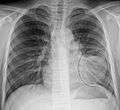

| A chest X-ray showing a very prominent wedge-shape bacterial pneumonia in the right lung. | |

- Normal AP CXR

AP CXR showing left lower lobe pneumonia associated with a small left sided pleural effusion

AP CXR showing right lower lobe pneumonia

AP CXR showing pneumonia of the lingula of the left lung

Right upper lobe pneumonia as marked by the circle.- Left upper lobe pneumonia with a small pleural effusion.

- Right lower lobe pneumonia as seen on a lateral CXR